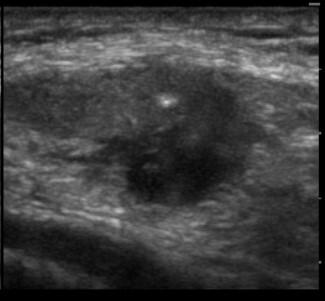

Knee Patellar Tendinosis Transverse Axis Image